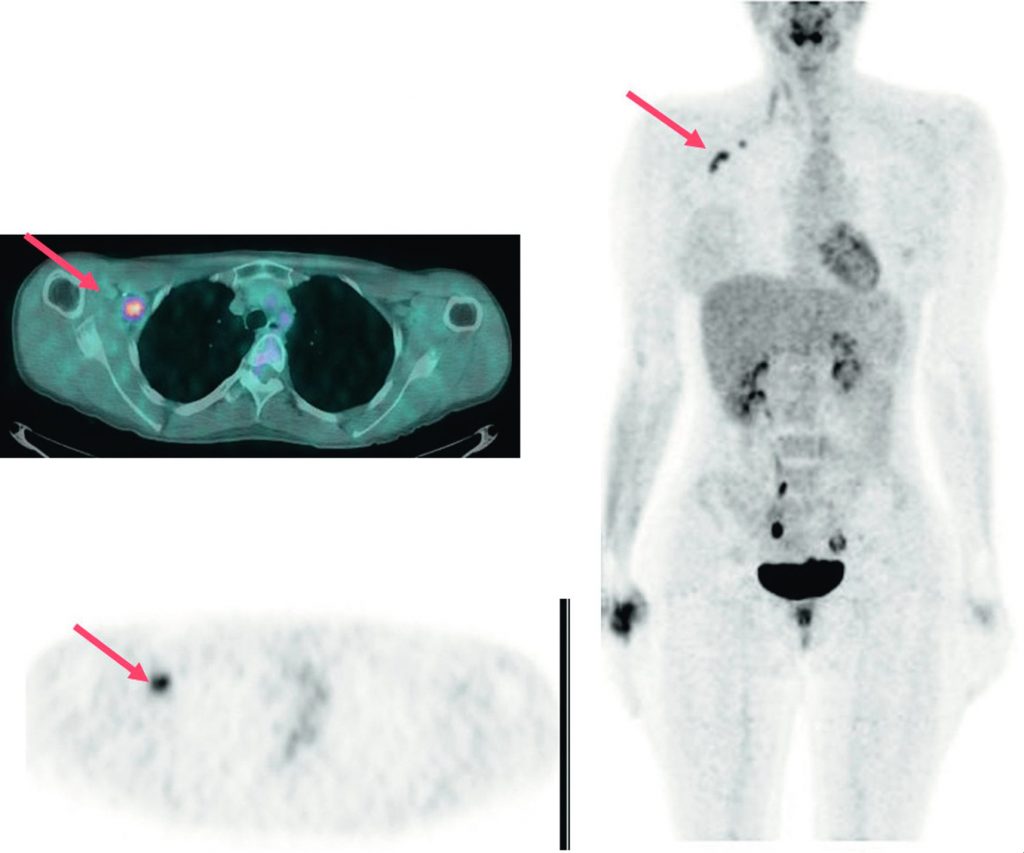

La TEP-TDM au 18FDG est recommandée en cas de récidive prouvée ou suspectée (figures 34.5 et 34.6).

Fig. 34.5 Dans le suivi d’une patiente pour cancer du sein droit, apparition d’une élévation du CA15-3 avec bilan morphologique négatif.

La TEP-TDM au 18FDG met en évidence une récidive axillaire droite bifocale isolée (flèche).

Source : CERF, CNEBMN, 2022.